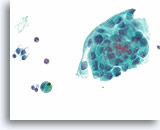

Afbeelding 13

Benigne, hyperplastisch/adenomatoïde nodule, schildklier FNA, celblok.

Het celblok dat overeenkomt met afbeelding 11-12 toont een duidelijk bijvoeging van micro- en macrofollikels. Er zijn twee kenmerken die voor een benigne nodule pleiten. Het eerste is dat de microfollikels afgeplat cytoplasma vertonen, vergeleken met de robuuster uitziende macrofolliculaire cellen (vergelijk de hoogte van het cytoplasma bij de twee pijlen). Een tweede kenmerk is de variatie in het uiterlijk van het colloïd tussen de verschillende follikels. Let op het oedemateuze colloïd in het ene follikel dat zich naast een follikel bevindt met dicht opeengepakt colloïd (open pijlen). Van benigne hyperplastisch/adenomatoïde nodulen wordt verwacht dat ze heterogeniteit vertonen, terwijl folliculaire neoplasmen monotoner zijn.

40X

Afbeelding 13

Benigne, hyperplastisch/adenomatoïde nodule, schildklier FNA, celblok.

Het celblok dat overeenkomt met afbeelding 11-12 toont een duidelijk bijvoeging van micro- en macrofollikels. Er zijn twee kenmerken die voor een benigne nodule pleiten. Het eerste is dat de microfollikels afgeplat cytoplasma vertonen, vergeleken met de robuuster uitziende macrofolliculaire cellen (vergelijk de hoogte van het cytoplasma bij de twee pijlen). Een tweede kenmerk is de variatie in het uiterlijk van het colloïd tussen de verschillende follikels. Let op het oedemateuze colloïd in het ene follikel dat zich naast een follikel bevindt met dicht opeengepakt colloïd (open pijlen). Van benigne hyperplastisch/adenomatoïde nodulen wordt verwacht dat ze heterogeniteit vertonen, terwijl folliculaire neoplasmen monotoner zijn.

40X